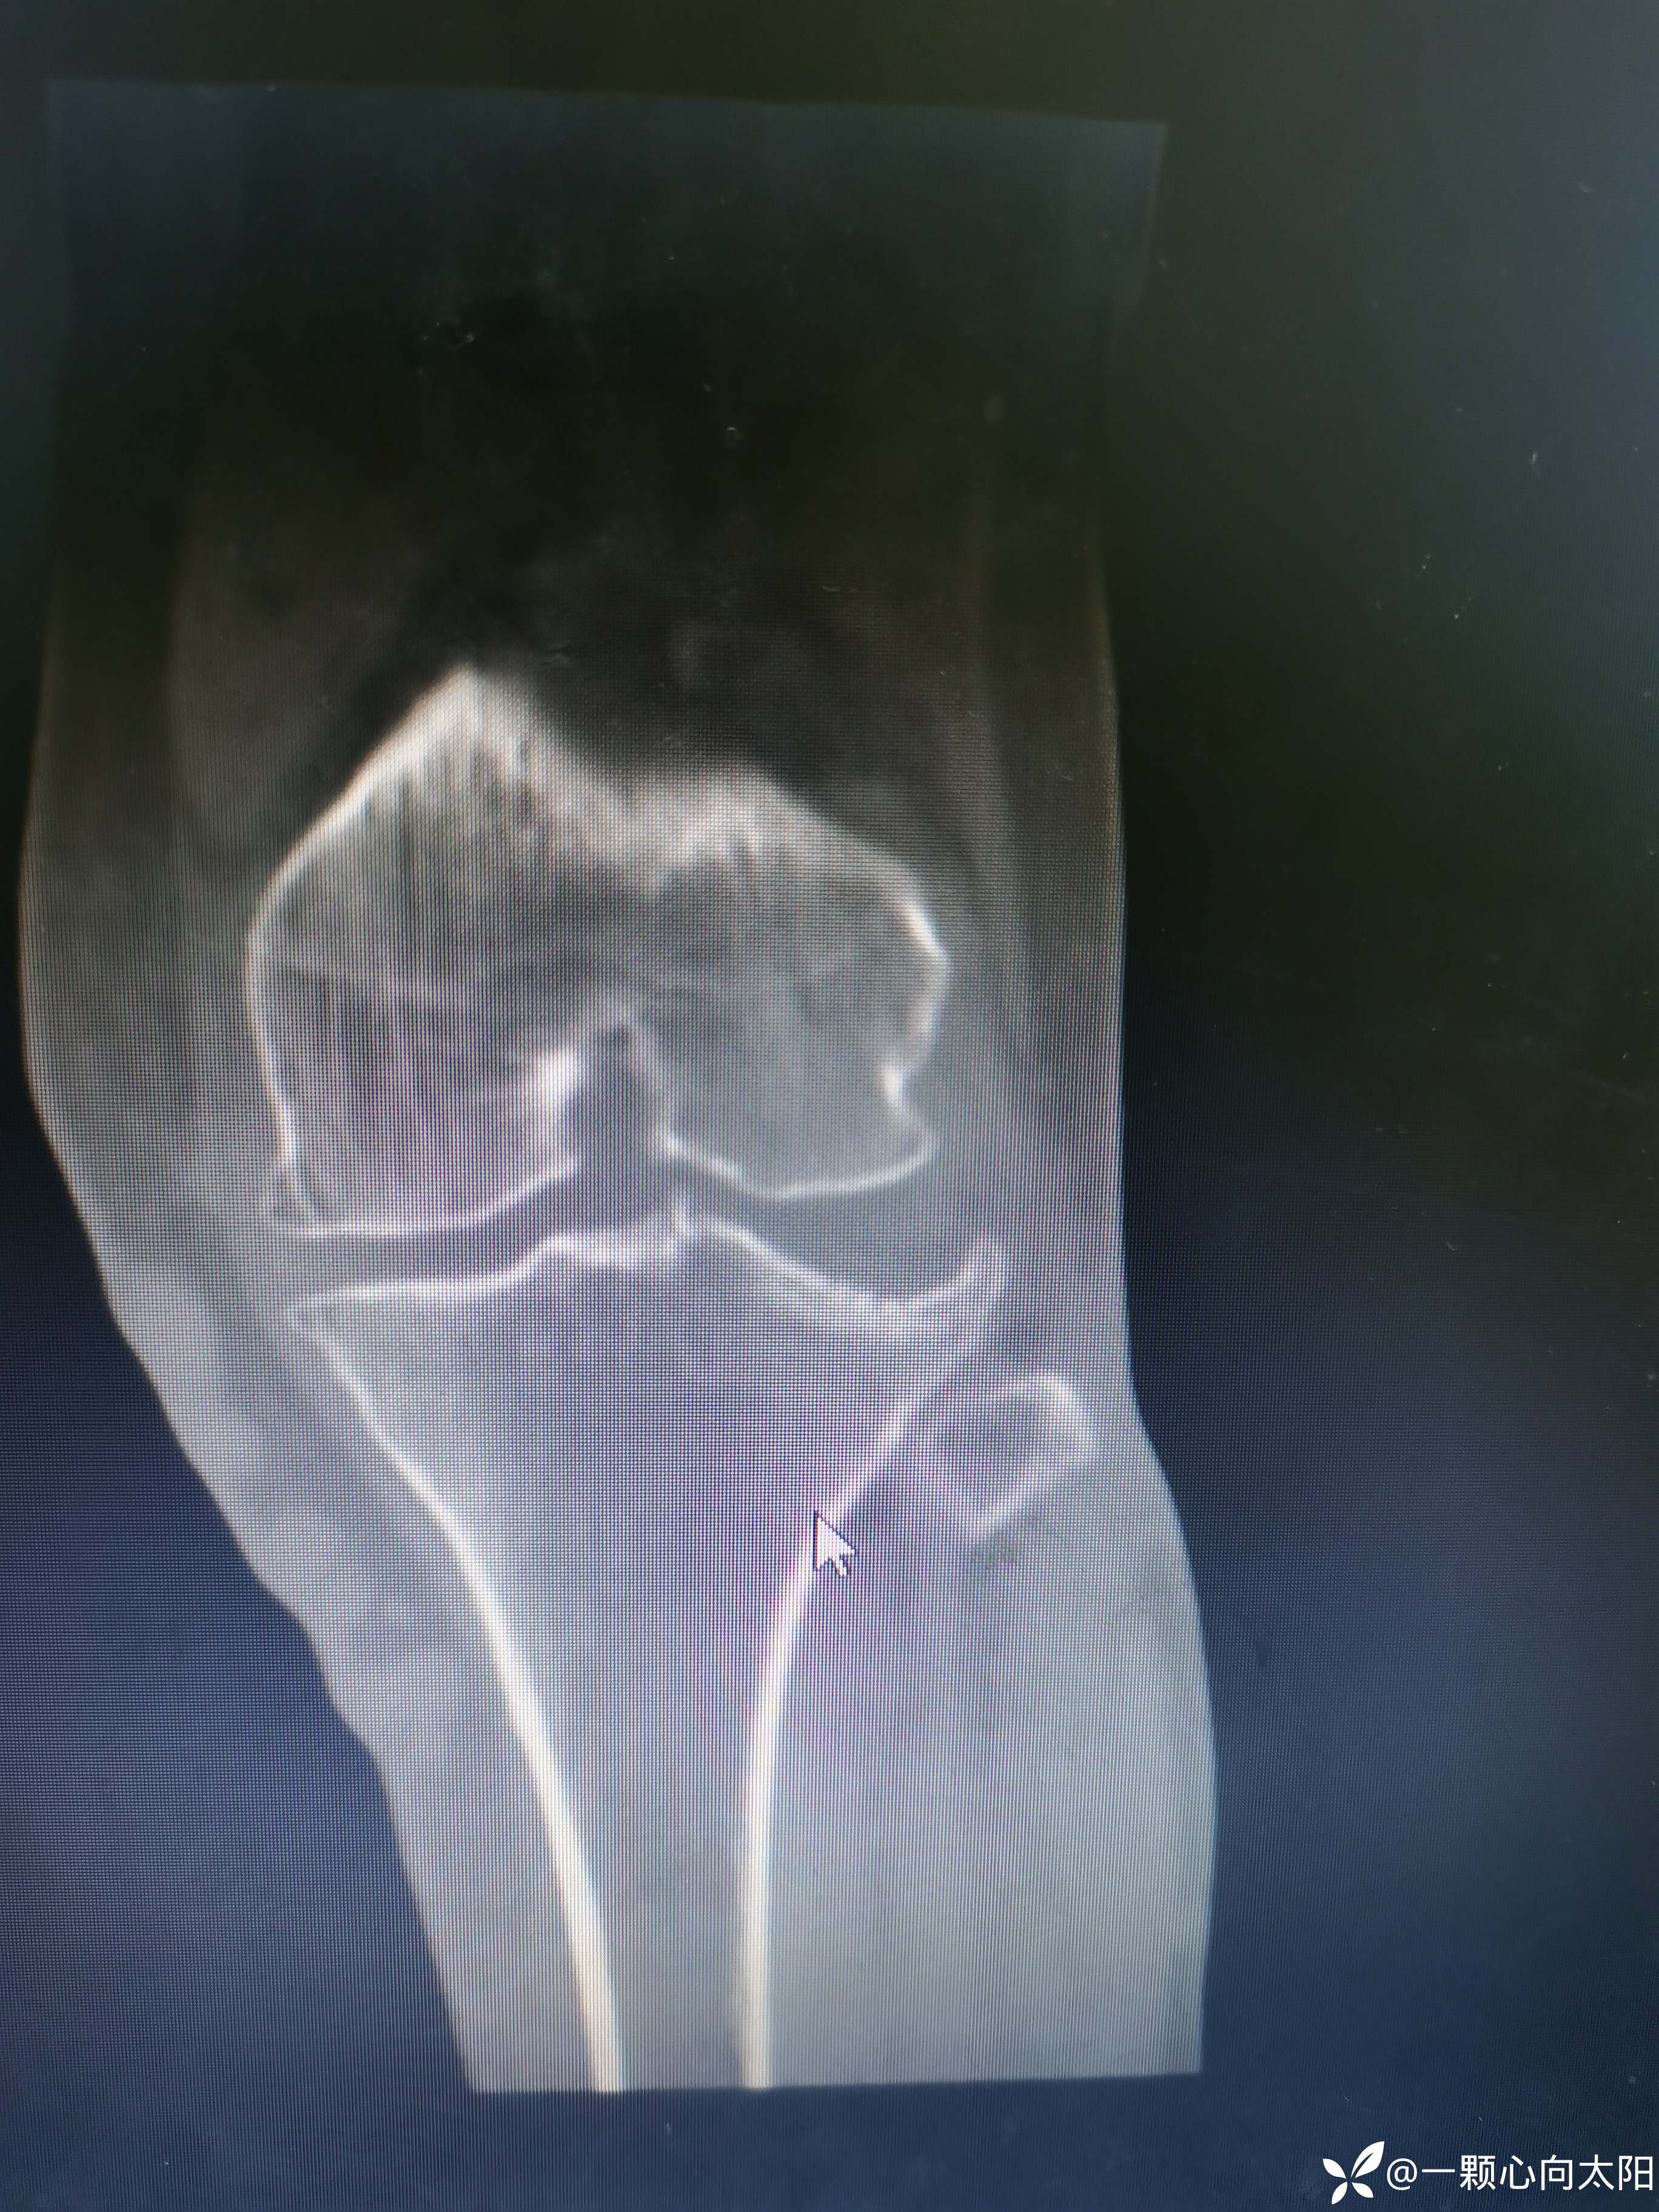

69岁,女性患者,以“外伤致左膝关节疼痛伴活动受限3小时”为主诉入院。